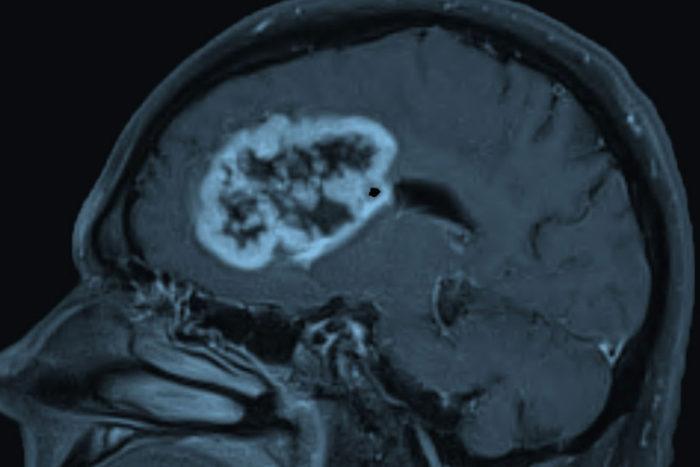

Beyin malign neoplazmının tanısında çeşitli görüntüleme yöntemleri kullanılır. Manyetik rezonans görüntüleme (MR) ve bilgisayarlı tomografi (BT), tümörlerin boyutunu, yerini ve türünü belirlemek için kullanılan başlıca tanı yöntemleridir. Bu görüntüleme yöntemleri, tümörün beyindeki etkilerini ve çevre dokulara yayılma durumunu değerlendirir. Gerekli durumlarda, kesin tanı için biyopsi yapılabilir.